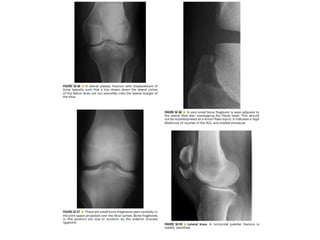

Skeletal trauma was presented by Dr Laith Fadhel with reference to Grainger's Diagnostic Radiology textbook. The presentation covered skeletal trauma as assessed through diagnostic radiology techniques. Key findings and treatments for skeletal injuries were likely discussed.